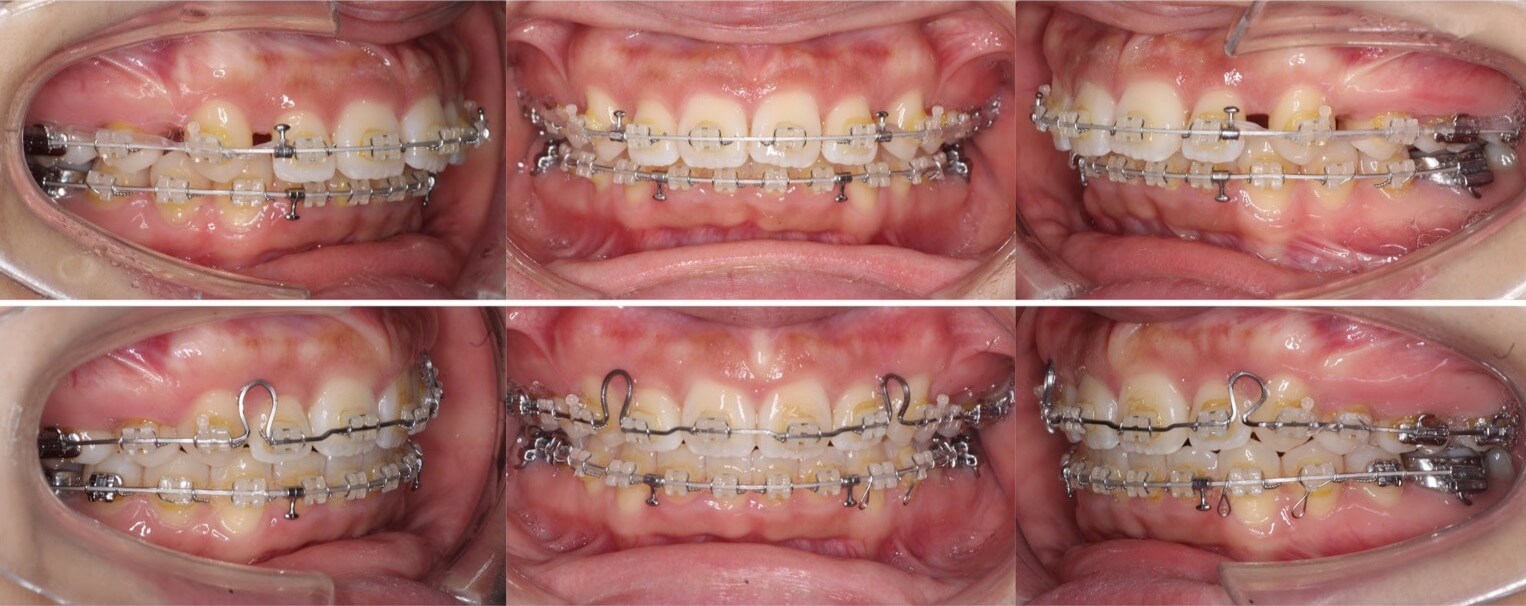

大学生男性・唇側矯正装置・4本抜歯

口元の突出もある重度の過蓋咬合症例は、表側矯正装置の方が確実に治療が可能です。このようなケースの治療期間は3年を超えてしまいます。側方のシザースバイトも併発しているため、下の歯並びにブラケット装置を装着する面積を確保する事に苦戦しました。治療途中は何回もワイヤーが上の歯で噛み切ってしまい折れてしまうため、複雑なワイヤーを併用する事で過蓋咬合を改善しました。

<症例概要>

主訴:口元の突出

年齢・性別:大学生男性

住まい:千葉県八千代市

症状:過蓋咬合・上下顎前突・左側シザースバイト

治療方針:抜歯空隙の閉鎖(最大固定)

治療装置:唇側矯正装置

固定装置:歯科矯正用アンカースクリュー(上頬側x2)

抜歯:上下左右4番(計4本)

治療期間:3年2か月

リテーナー:下フィックスタイプ+上下プレートタイプ

治療費用:968,000(税込)

代表的副作用:痛み・治療後の後戻り・歯根吸収・歯髄壊死・歯肉退縮

▶︎その他の副作用